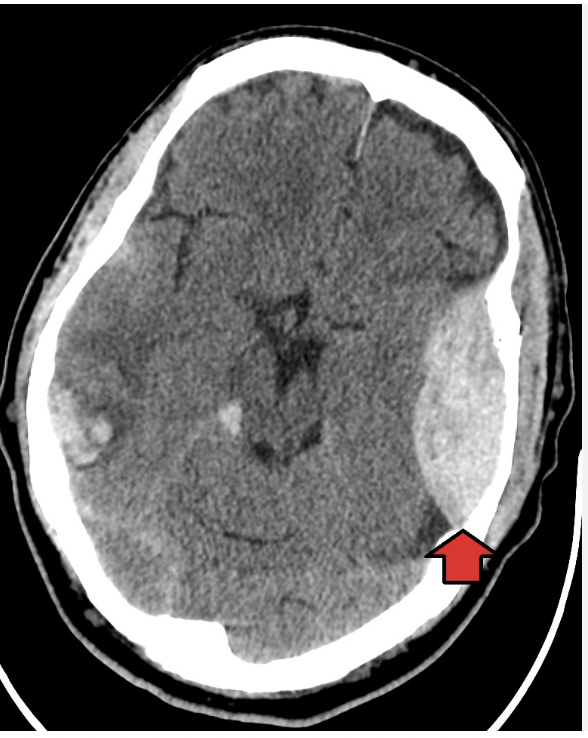

Origen de un hematoma subdural

Es de origen venoso y sigue las suturas del cerebro, tiene forma de media luna o de platano o semiluna.

• Evolución lenta

No hay barrera, si pasa las suturas

Q

origen de un hematoma epidural

A

Es de origen arterial, no puede atravesar las suturas

en forma de balón de americano, limón, biconvexo, bolillo

-Es de evolución rápida, se deterioran rápido

Como se ve el edema cerebral

Se ve borramiento de circunvoluciones y cisternas, no se puede diferencia S.gris de blanca, ventrículos, etc

El liquido pasa al intesrticio